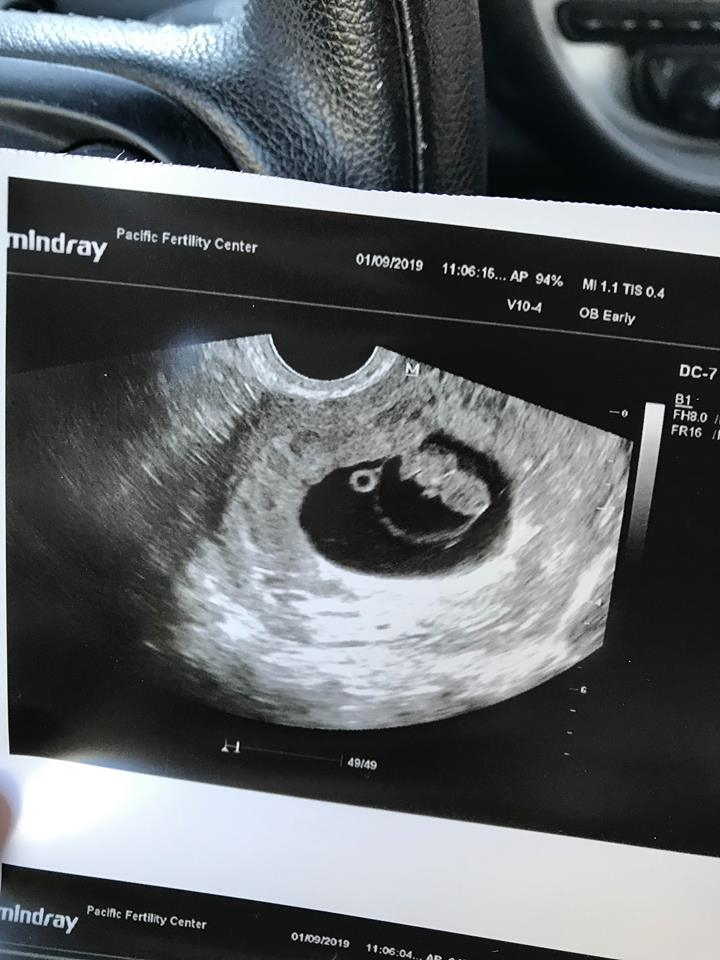

8w3d today. I completely freaked out thinking there would be awful news. I sat there praying in agony because I truly don't think I have another IVF in me. My ass is sore and numb from the shots. When I heard his heart beat (185), all of my fears, in that moment, melted away. Complete awe is the only way to describe it. All I wanted to do was listen to it forever. My rainbow. My little boy. I have a little baby. I'm someone's Mother

It’s a nugget! Measuring 9w4d, heartbeat of 175. 😍😍😍